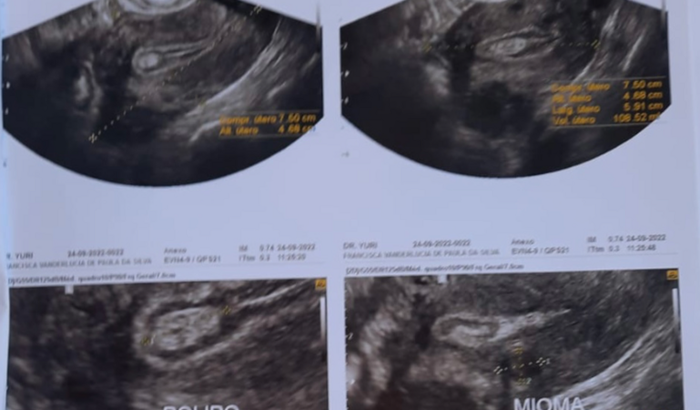

A 15 dias em exames de rotina descobri alguns nódulos até então benignos, porém se faz necessário a retirada de todo útero, onde moro não é tão fácil assim de fazer esse procedimento e nem equipamentos para isso tem.